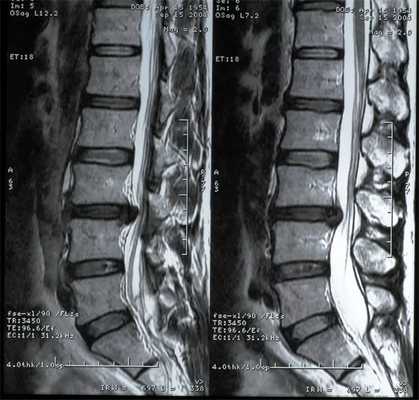

(Справа) Миелограмма в прямой проекции: типичная картина объединенных корешков спинного мозга — видна большого размера дуральная воронка, содержащая два корешка (L5, S1), каждый из которых, однако, покидает спинномозговой канал через соответствующее межпозвонковое отверстие. (Слева) MPT, Т1-ВИ, сагиттальная проекция (объединенные корешки L5 и S1): корешки покидают спинномозговой канал независимо друг от друга через соответствующие им межпозвонковые отверстия. Это наиболее распространенный анатомический вариант объединения корешков спинного мозга.

(Справа) На аксиальном Т2-ВИ (объединенные корешки L5 и S1) визуализируются типичные анатомические особенности при объединении корешков спинного мозга: дуральная воронка справа необычно расширена, берет начало выше, чем обычно, и содержит в себе два отдельных корешка.